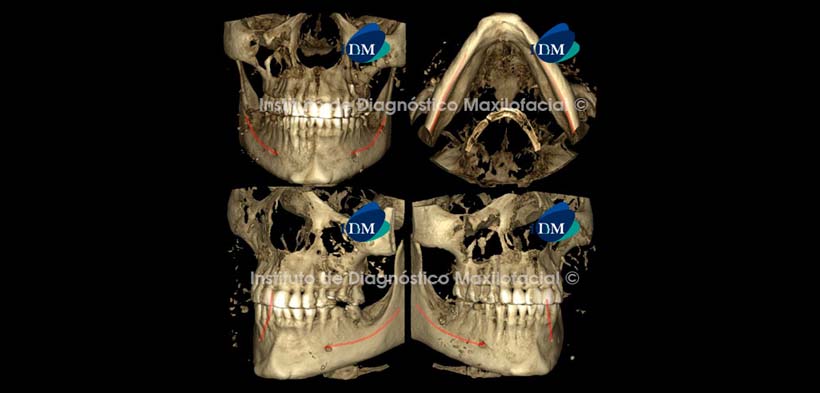

La reconstrucción 3D en la opción radiográfico matizado nos muestra preponderantemente las estructuras con alto contenido mineral como el tejido óseo. En este caso las calcificaciones en tejidos blandos son visualizadas con un aspecto puntiforme y con una distribución irregular (Fig. 6).